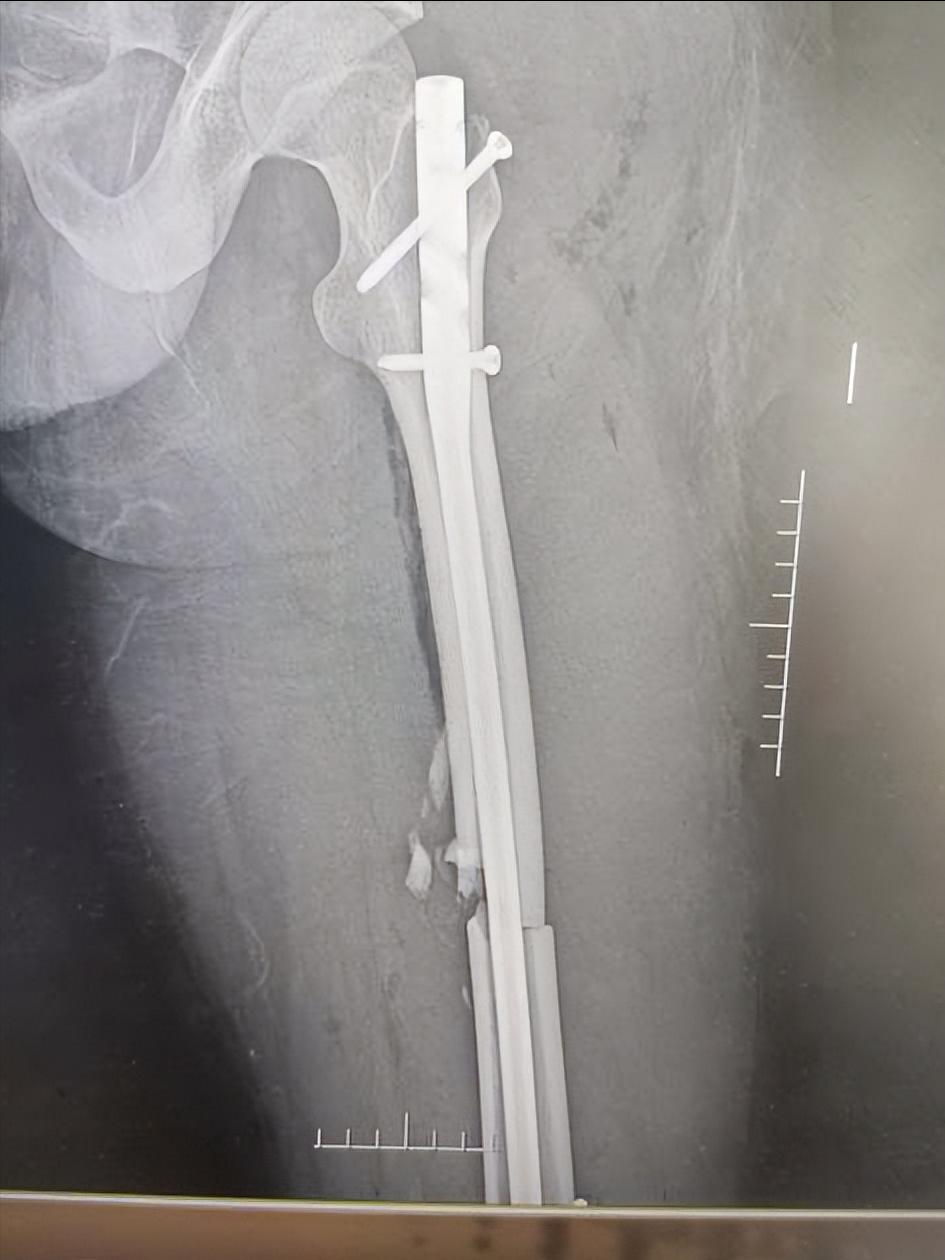

弹性髓内针内固定

学龄前期儿童心智尚不成熟,常不配合治疗,可影响治疗效果,严重时可能导致畸形 。随着社会的发展,人们对恢复患儿伤肢功能及解剖完整性要求日益提高,并希望尽早恢复患儿学习、生活能力。

近年来伴随着骨科植入器械、手术技术的不断发展,学龄前期儿童股骨干骨折手术治疗也逐渐增多。儿童骨折手术主张微创治疗,注重骨折复位时要求尽量减少手术损伤,弹性髓内针内固定技术为微创治疗的典型代表 :

即利用三点固定原理对骨折弹性固定,防止再移位、成角和旋转,骨折断端无应力遮挡,能促进骨痂生长及塑形,伤肢负重活动早,髋、膝关节功能恢复好 。弹性髓内针固定最佳适应证是股骨干横形、短斜形、螺旋形骨折及干骺端骨折。

近年来弹性髓内针适应证被放宽到长度不稳定型即粉碎性或长斜型、长螺旋型股骨干骨折。 配合尾帽固定能更好的维持股骨干的长度,且能预防弹性钉自股骨远端进钉点退出。如闭合复位仅在开孔处遗留微小疤痕,外观美观 。

但也有其不足,如弹性髓内针内固定需完善术前系列检查、准备,内固定器材价格较高,术后需严密的术后监测,故整体治疗费用较高 。弹性髓内针内固定技术最常见的并发症是针尾激惹,为在骨皮质外保留的钉尾过长或及钉尾折弯角度过大所致

表现为膝关节内外侧软组织在针尾部处长时间摩擦形成假性囊肿, 呈稍微隆凸的包块,触摸时可感觉到包块内针尾的存在,轻微压痛,在取内固定时切开可见囊肿内滑膜增生,有淡黄色的浆液及豆腐渣样物质沉淀。

膝关节内外侧假性囊肿可致患儿因疼痛不敢活动而发生膝关节僵硬。如弹性髓内针直径过大导致进针时致骨皮质劈等并发症 。骨折愈合后均需行弹性髓内针内固定取出,由于学龄前期儿童难以配合,大多需住院麻醉下进行,二次治疗费用高。